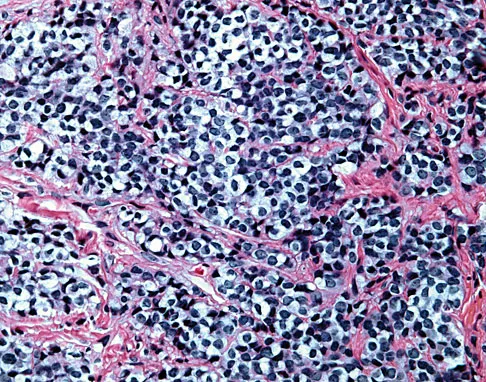

A radiograph, MRI scans, and a biopsy specimen of a 9-year-old boy with thigh pain are shown in Figures 37a through 37d. Management should consist of

The patient has Ewing's sarcoma. Management options for local tumor control include radiation therapy, resection, or a combination; however, in this patient wide resection is preferred over radiation therapy. Radiation therapy is associated with damage to the growth plate, pathologic fracture, radiation-induced sarcomas, and a local recurrence rate of approximately 10% to 12%. Radiation therapy is used for positive margins, unresectable tumors, or for tumors that have a poor response to chemotherapy. Amputation is not necessary since the tumor is resectable. Chemotherapy has improved overall survival rates to over 60% of patients. Sailer SL: The role of radiation therapy in localized Ewing' sarcoma. Semin Radiat Oncol 1997;7:225-235. Shankar AG, Pinkerton CR, Atra A, Ashley S, Lewis I, Spooner D, et al: Local therapy and other factors influencing site of relapse in patients with localised Ewing's sarcoma. United Kingdom Children's Cancer Study Group (UKCCSG). Eur J Cancer 1999;35:1698-1704. Carrie C, Mascard E, Gomez F, Habrand JL, Alapetite C, Oberlin O, et al: Nonmetastatic pelvic Ewing sarcoma: Report of the French society of pediatric oncology. Med Pediatr Oncol 1999;33:444-449.